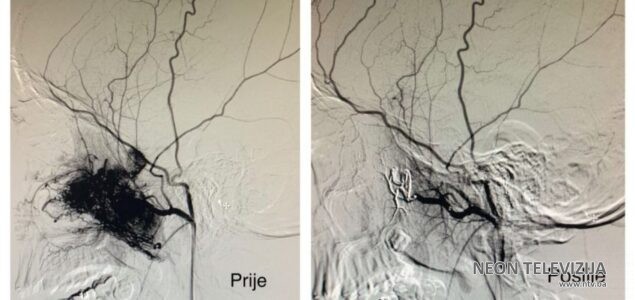

Prema riječima jednog od operatora dr. Hasana Altumbabića, mr. med. sc., prvo se pokušava zaustaviti dotok krvi u arterije koje opskrbljuju tumor, odnosno radi se transkateterska embolizacija, a nakon toga hirurškim putem se odstranjuje tumor. U slučaju da se tumor proširio na moždanu šupljinu i da se ne može odstraniti hirurškim putem primjenjuje se radioterapija. “Naš pacijent je 14-godišnji dječak koji je prije 6 mjeseci imao saobraćajnu nesreću, a unazad 3 mjeseca ne diše na desnu nosnicu i ima česta krvarenja iz iste. Nakon dodatnih neuroradioloških pretraga i CT angiografije, postavljena je sumnja na juvenilni angiofibrom, koji je destruirao unutarnji zid očne duplje i dijelom bazu mozga sa endokranijalnom propagacijom, te je indicirano operativno liječenje”, rekao je dr. Altumbabić i pojasnio da je u prvom aktu na Klinici za neurohirurgiju urađena embolizacija krvnih sudova angiofibroma, koja je protekla uredno i bez komplikacija, nakon čega se u drugom aktu, na Klinici za bolesti uha, grla i nosa pristupilo hiruškom odstranjivanju tumora, gdje je tumor u cijelosti odstranjen, a nastali defekt rekonstruiran. Kako je istakao dr. Altumbabić, rani postoperativni oporavak pacijenta protiče uredno.